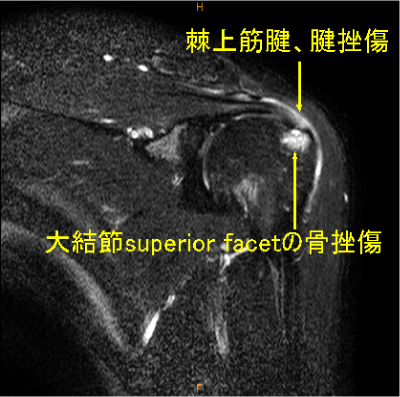

大結節前方(superior facet)の骨変化は棘上筋腱の損傷を高頻度に合併している。

長頭腱腱挫傷, 大結節の骨挫傷, 棘上筋腱腱挫傷